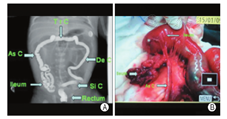

孕妇,31岁,孕2产1,孕期体健,否认孕期用药史,育有一女,2岁体健。孕26+3周行胎儿产前系统超声检查,超声显示:单活胎,生长指标可,羊水过多;小肠管广泛扩张、积液,内径最宽处约1.4 cm;胎儿腹内混合性团块,大小约4.2 cm×3.7 cm×3.2 cm,较固定,与周围组织分界不清;扩张肠管远端显示不满意。超声诊断:胎儿肠管扩张,小肠肠管狭窄或闭锁可能,继发性胎粪性腹膜炎?远端肠管显示不满意(图1)。后陆续进行胎儿超声心动图检查、定期孕期保健及超声随诊,未发现胎儿伴发其他畸形及染色体异常。在当地医院分娩一男婴,出生时即发现全腹膨隆伴口唇发绀,大便未解。全腹CT示:肠管明显扩张,直肠及乙状结肠空虚状伴腔内密度较高,腹腔内多发钙化灶。出生后2 d上述症状不减,遂转至我院小儿外科,门诊拟"①新生儿肠梗阻:先天性肠闭锁?胎粪性腹膜炎?②新生儿肺炎"收住入院。腹部X线检查示:肠腔积气积液。超声检查:房间隔缺损,肝、胆、脾、胰、双肾、输尿管、膀胱未见明显超声异常,腹腔内见多发钙化灶,肠管广泛扩张,最宽处约2.2 cm,考虑肠梗阻、继发性胎粪性腹膜炎可能。结肠造影示:小肠梗阻;结肠管腔较细,结肠袋未显示,结肠细小症?(图2A)。

行急诊剖腹探查,手术所见:肠管与肠管、肠系膜、腹壁、右侧肝脏之间均呈广泛膜状、索带状粘连,部分粘连索带及系膜可见散在钙化斑。回盲部至回肠约50 cm处回肠闭锁,近端肠管扩张明显,直径约4 cm,肠管壁肥厚水肿,内有较多积气积液,闭锁远端小肠直径约0.6 cm,呈萎瘪状,两盲端分离,系膜呈"V"型缺损,测量近侧盲端肠管至屈氏韧带长约60 cm(图2B)。术中诊断:①先天性肠闭锁(ⅢA型);②梗阻型胎粪性腹膜炎;③广泛肠粘连;④结肠细小症。行先天性肠闭锁成形术+肠粘连松解术,术后第2 d有少量黄绿色黏液便排出,术后第3 d有少许墨绿色糊状便排出,术后第8 d进食糖水后无明显腹痛腹胀等不适,大小便无异常。